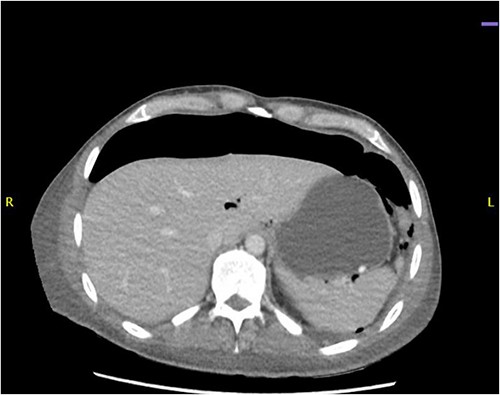

CT abdomen revealed a large amount of free air throughout the abdomen, mostly localized anterior, but also perihepatic, perigastric, paracolic, and perisplenic (Figs 1 and 2).

CT abdomen showing large amount of free air throughout the abdomen.